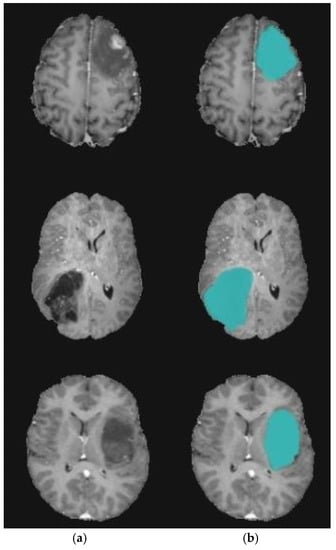

3.3. Level Set Segmentation

| 1: Insert initial contour points using two-step DA clustering output (ROI indexes). 2: Construct a signed distance function. 3: Calculate feature image using Gaussian filter and gradient. 4: Obtain the curve’s narrow band. 5: Obtain curvature and use gradient descent to minimize energy. 6: Evolve the curve. 7: Repeat step number two and stop after obtaining the segmented region. |